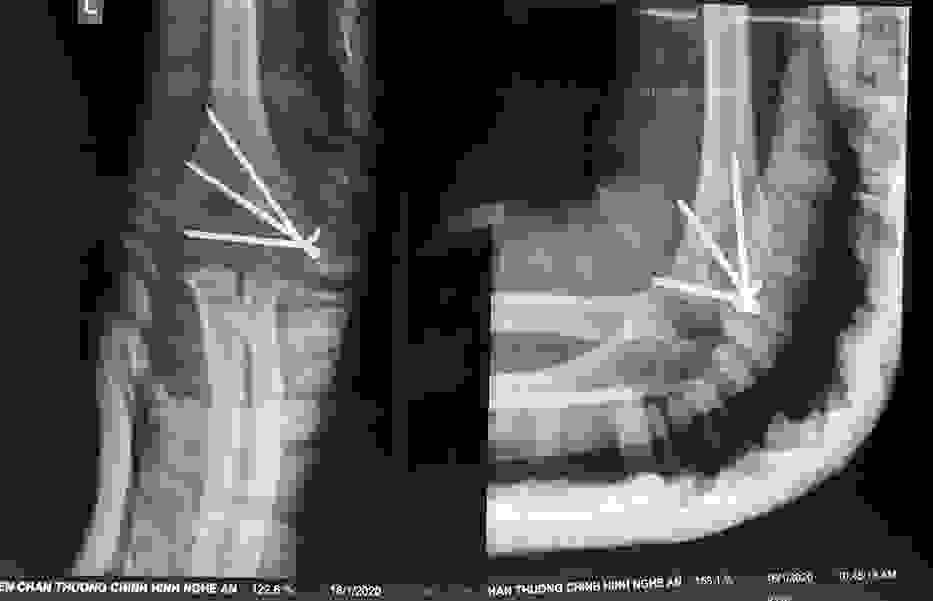

Phẫu thuật thành công ca bệnh hiếm gặp...khớp giả bẩm sinh xương chày

26/06/2019 17:00

Đã xem: 3703

Bệnh viện Chấn thương- Chỉnh hình Nghệ An, vừa phẫu thuật thành công cho bệnh nhi khớp giả bẩm sinh xương chày